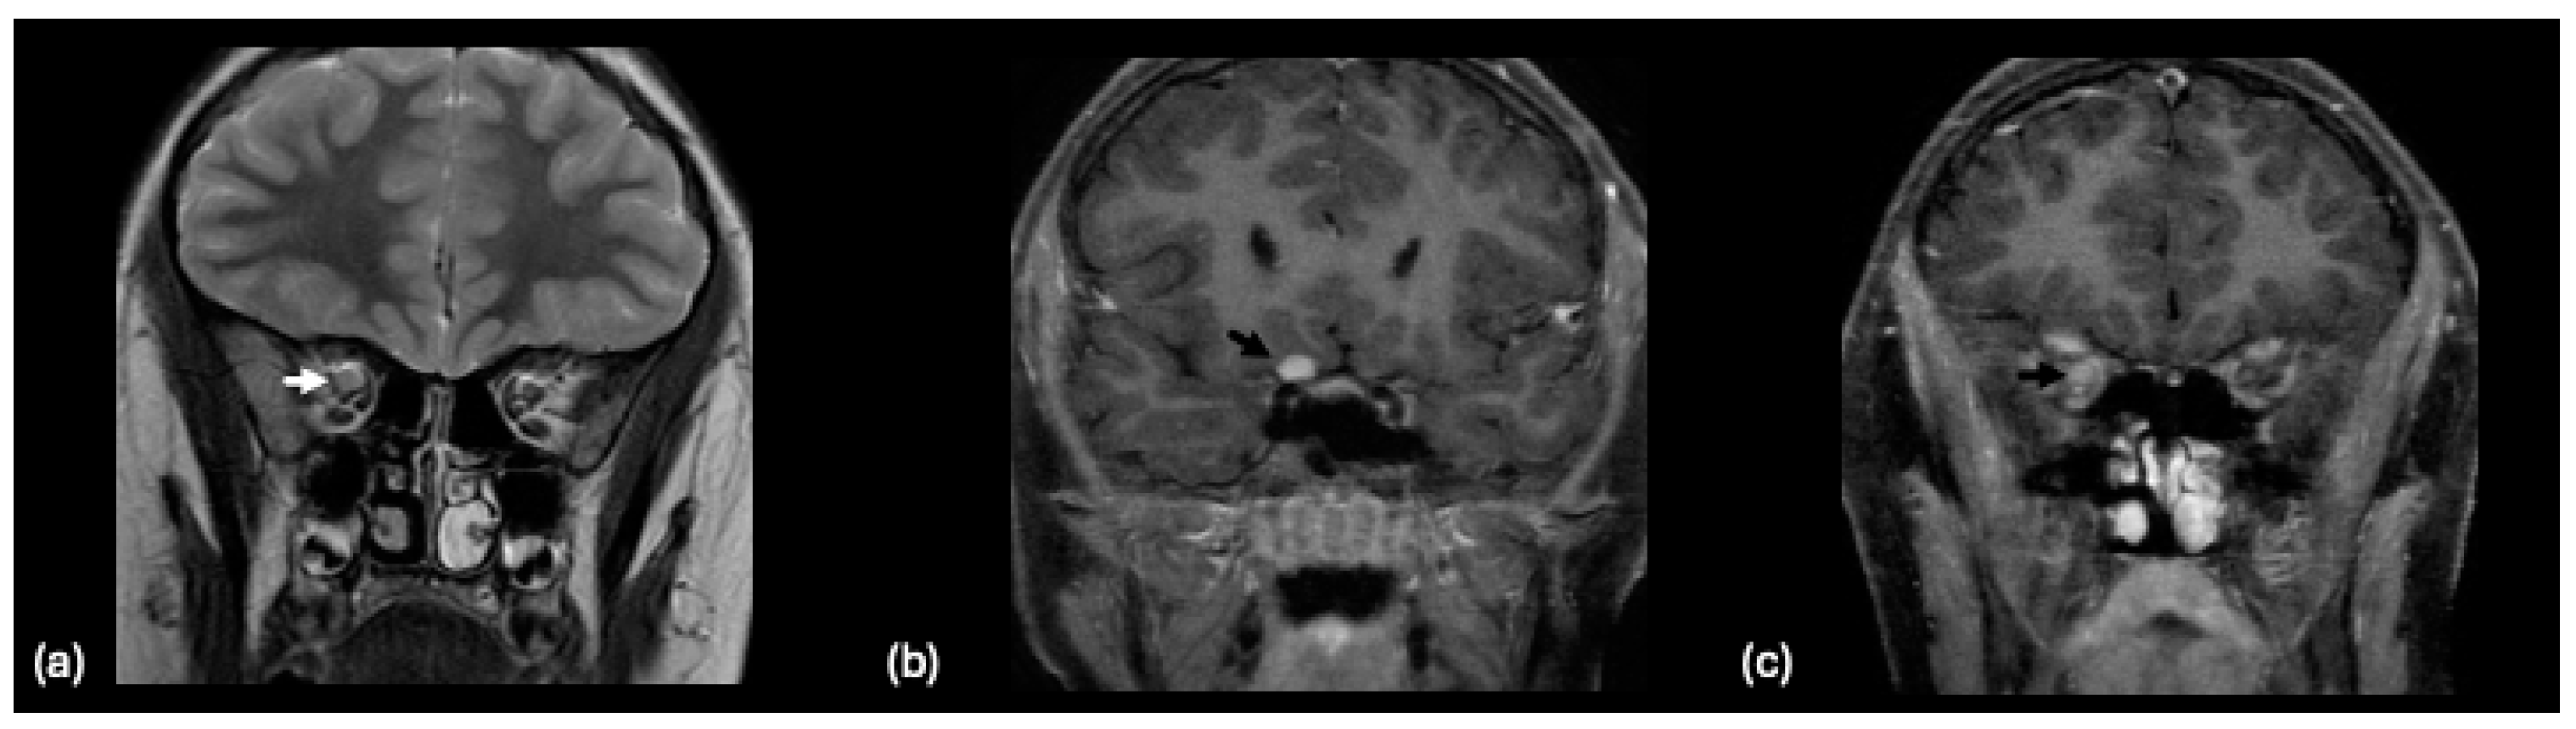

- Dutra, B.G.; da Rocha, A.J.; Nunes, R.H.; Maia, A.C.M. Neuromyelitis Optica Spectrum Disorders: Spectrum of MR Imaging Findings and Their Differential Diagnosis. RadioGraphics 2018, 38, 169–193. [Google Scholar] [CrossRef] [PubMed]

- Absoud, M.; Lim, M.J.; Appleton, R.; Jacob, A.; Kitley, J.; Leite, M.I.; Pike, M.G.; Vincent, A.; Wassmer, E.; Waters, P.; et al. Paediatric neuromyelitis optica: Clinical, MRI of the brain and prognostic features. J. Neurol. Neurosurg. Psychiatry 2015, 86, 470–472. [Google Scholar] [CrossRef] [PubMed]

- Bulut, E.; Karakaya, J.; Salama, S.; Levy, M.; Huisman, T.; Izbudak, I. Brain MRI Findings in Pediatric-Onset Neuromyelitis Optica Spectrum Disorder: Challenges in Differentiation from Acute Disseminated Encephalomyelitis. AJNR Am. J. Neuroradiol. 2019, 40, 726–731. [Google Scholar] [CrossRef]

- Banker, P.; Sonni, S.; Kister, I.; Loh, J.P.; Lui, Y.W. Pencil-thin ependymal enhancement in neuromyelitis optica spectrum disorders. Mult. Scler. 2012, 18, 1050–1053. [Google Scholar] [CrossRef] [PubMed]

- Kim, H.J.; Paul, F.; Lana-Peixoto, M.A.; Tenembaum, S.; Asgari, N.; Palace, J.; Klawiter, E.C.; Sato, D.K.; de Seze, J.; Wuerfel, J.; et al. MRI characteristics of neuromyelitis optica spectrum disorder: An international update. Neurology 2015, 84, 1165–1173. [Google Scholar] [CrossRef]